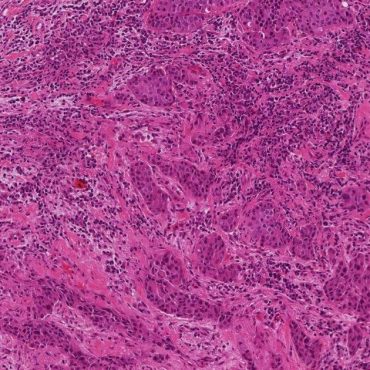

Over the past few years, Roberto Salgado, Sherene Loi and Carsten Denkert have developed the International Immuno-Oncology Biomarker Working Group on Breast Cancer, with members including expert clinical research groups, pathologists, clinicians and statisticians worldwide currently knowledgeable in the field of Immune-oncology Biomarkers. The purpose of this Working Group is to develop, in a timely manner, standards on the assessment of Immuno-Oncology Biomarkers to aid pathologists, clinicians and researchers in their research and daily practice.

All materials on this website, including images, annotations, and similar research and educational data, are anonymized and are therefore freely available to browse, download, and use for scientific and educational purposes.